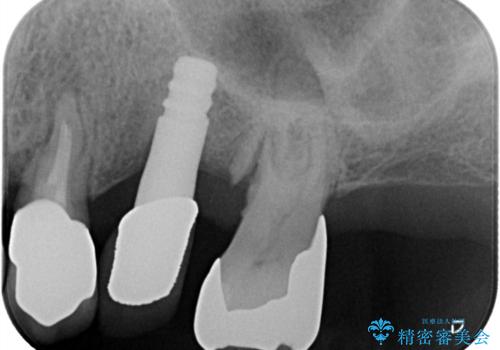

左上6番目の歯が根っこ部分で破折しており、噛むたびに痛みが生じる状態でした。

歯根破折により抜歯となり、インプラント治療(一回法)にて補綴修復を行いました。

抜歯から3か月程骨ができてくるのを待ってからインプラントを埋入しています。

埋入時には上顎洞粘膜を数ミリ挙上しています。